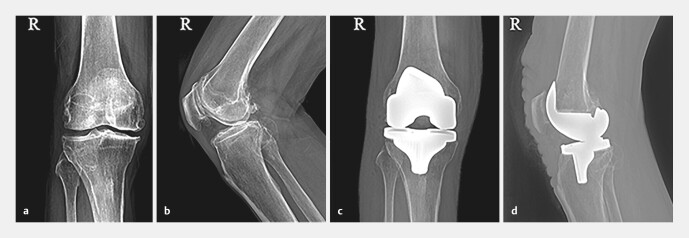

急性动脉栓塞是一个罕见的但是严重的并发症大家普遍认为,在这一情况下应立即进行再驱魔手术,但具体治疗仍未消除争议。关于两起动脉栓塞动脉血肿是动脉动脉出血引起的动手术后,两名患者右下肢体失去了知觉和行动,加上动脉器官dorsalis pedis严重恶化。心脏血管图显示大力心脏栓塞曾经有一位患者接受过内脏出血治疗,但此过程却导致右腿肌大面积感染和坏死,于是扫瞄成功后,急需经过多次肠道手术和皮肤移植。另一名患者进行了心室切除术、血管重建和预防性纤维性分裂;手术后,脚麻痹了,身体也不那么虚弱。本研究报告建议,外科医生对膝盖法老王应该给予相关的关注。手术前需要躺下并进行身体检查外科手术应该精确而小心地进行,手术后要仔细观察四肢感觉和血液循环。当脚跳不正常、动脉律动微弱时,应立即进行(多普勒超声波和动脉图谱)观察。一旦诊断出动脉血栓就必须立即恢复供血如果诊断时间延后6小时以上,预防性分泌物学可能是防止疾病发作的必要手段。

Die akute arterielle Embolie ist eine seltene, aber schwerwiegende Komplikation nach einer Knie-Totalendoprothese (Knie-TEP). Es besteht ein allgemeiner Konsens darüber, dass in dieser Situation sofort eine Revaskularisation durchgeführt werden muss, aber die spezifische Behandlung ist immer noch umstritten. Wir berichten über zwei Fälle von Embolien der Kniekehlenarterie, die durch eine akute arterielle Thrombose nach Knie-TEP verursacht wurden. Bei beiden Patienten kam es nach der Operation zu einem Gefühls- und Bewegungsverlust der rechten unteren Extremität und einer Pulsationsschwächung der Arteria dorsalis pedis; eine Angiografie zeigte eine Embolie der Arteria poplitea. Einer der Patienten erhielt eine Thrombolysetherapie, entwickelte jedoch eine großflächige Infektion und Nekrose des rechten Wadenmuskels und benötigte nach erfolgreicher Thrombolyse ein mehrfaches Debridement und Hauttransplantationen. Bei dem anderen Patienten wurde eine Thrombektomie, eine Gefäßrekonstruktion und eine prophylaktische Fasziotomie durchgeführt; nach der Operation blieben ein Taubheitsgefühl im Fuß und eine leichte Streckschwäche zurück. Die Autoren empfehlen Chirurgen, Hochrisikopatienten mit Knie-TEP eine angemessene Aufmerksamkeit zu widmen. Vor der Operation sind eine sorgfältige Anamnese und körperliche Untersuchung erforderlich. Der chirurgische Eingriff sollte präzise und schonend durchgeführt werden, nach der Operation sind das Gefühl der Gliedmaßen und die Blutzirkulation aufmerksam zu beobachten. Bei abnormalem Fußgefühl und schwacher arterieller Pulsation sollten umgehend erforderliche Untersuchungen (Doppler-Ultraschall und Arteriografie) durchgeführt werden. Wenn eine arterielle Thrombose diagnostiziert wurde, muss die Blutversorgung sofort wiederhergestellt werden. Verzögert sich die Diagnose um mehr als 6 Stunden, kann eine prophylaktische Fasziotomie erforderlich sein, um nachteilige Folgen zu vermeiden.